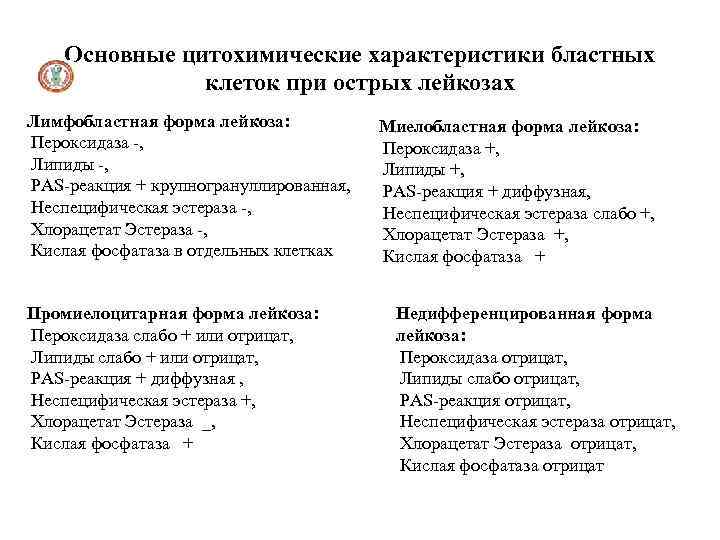

Основные цитохимические характеристики бластных клеток при острых лейкозах Лимфобластная форма лейкоза: Пероксидаза -, Липиды -, PAS-реакция + крупногрануллированная, Неспецифическая эстераза -, Хлорацетат Эстераза -, Кислая фосфатаза в отдельных клетках Промиелоцитарная форма лейкоза: Пероксидаза слабо + или отрицат, Липиды слабо + или отрицат, PAS-реакция + диффузная , Неспецифическая эстераза +, Хлорацетат Эстераза _, Кислая фосфатаза + Миелобластная форма лейкоза: Пероксидаза +, Липиды +, PAS-реакция + диффузная, Неспецифическая эстераза слабо +, Хлорацетат Эстераза +, Кислая фосфатаза + Недифференцированная форма лейкоза: Пероксидаза отрицат, Липиды слабо отрицат, PAS-реакция отрицат, Неспецифическая эстераза отрицат, Хлорацетат Эстераза отрицат, Кислая фосфатаза отрицат